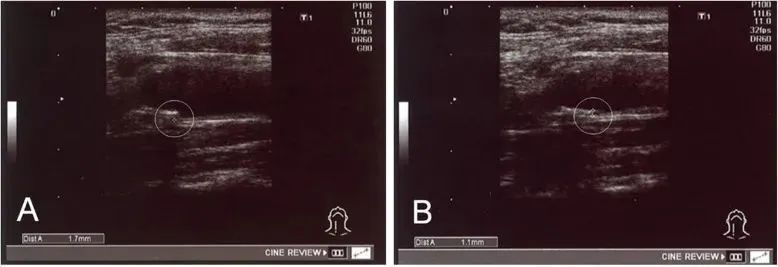

②、18例IMT值异常(≥1.1 mm)的患者,在治疗后IMT值均显著减少;

经过治疗,实验中一名患者 IMT 从 1.7 毫米降至 1.1 毫米

实验证实:干细胞可以改善血清中的高密度脂蛋白,低密度脂蛋白和残余样颗粒胆固醇水平,调节脂质代谢,能够安全有效地改善动脉粥样硬化。